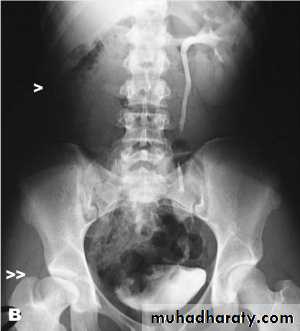

LT SIDED VUR ( HN&HN ) NEUROGENIC BLADDER Christmas tree sign

BPH with elevated bladder base